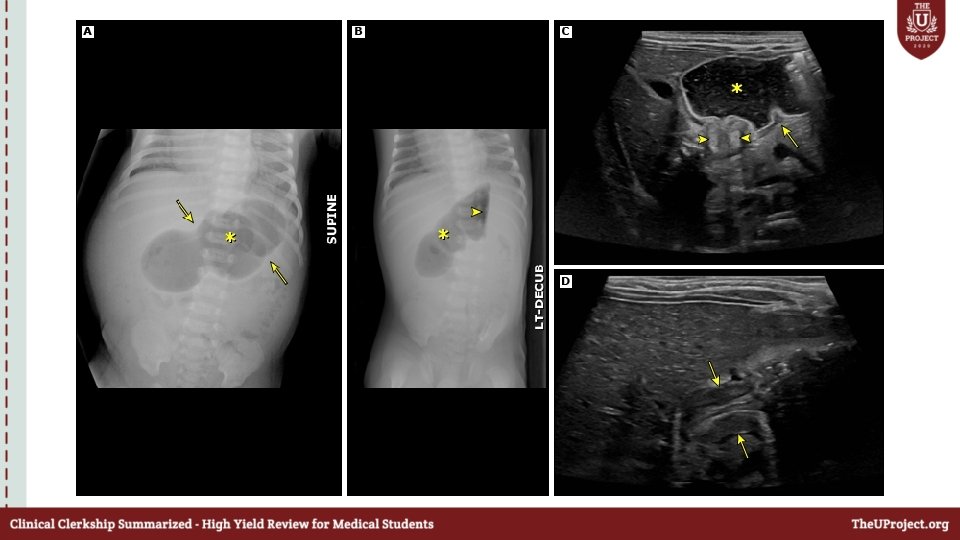

Free fluid with no solid organ injury What injuries will u expect & what should you do next ?